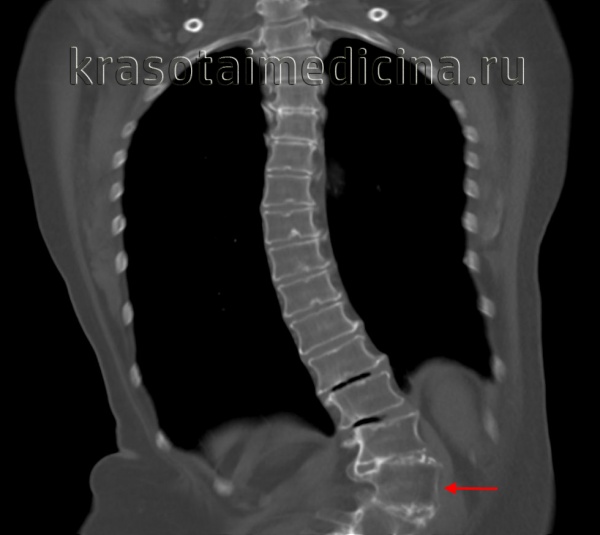

КТ ОГК. Тяжелая левосторонняя сколиотическая деформация грудопоясничного перехода.